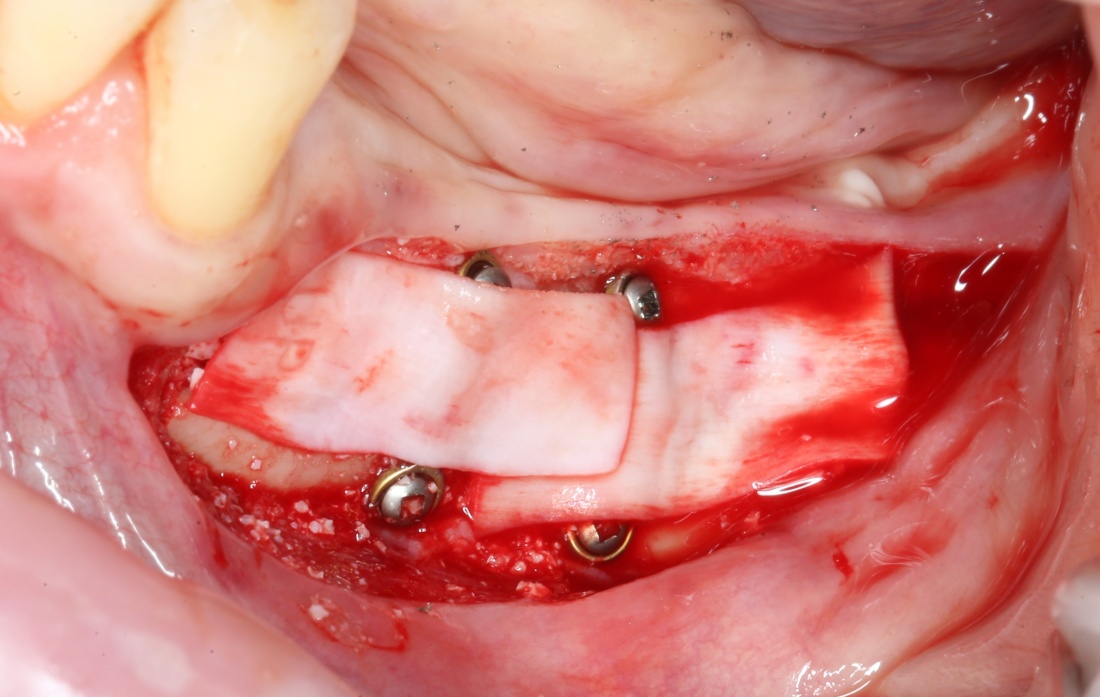

В какой момент это делать? Наверное, если Вы используете графт в виде твердого блока, то, мне кажется. разумнее сначала уложить графт, затем проводить фиксацию перемещенного костного фрагмента винтами или минипластинами:

И наоборот, если вы применяете графт в виде гранул (типа, Bio-Oss L), то, для начала, нужно зафиксировать костный фрагмент, затем укладывать графт.

8. Изоляция области дефекта с помощью барьерной мембраны.

Этот этап не представляет особых сложностей. Порядок действий зависит от того, какую барьерную мембрану Вы используете — некоторые из них нужно предварительно размочить в дистиллированной воде или физрастворе. А некоторые из них обладают достаточной гидрофильностью, чтобы мгновенно пропитаться кровью и стать липкими и эластичными прямо на месте.

Фиксировать барьерную мембрану не нужно. Она выполняет изолирующую функцию, каркасом формы не является. Правда некоторые виды барьерных мембран укладываются плохо, постоянно съезжают — в таких случаях, пара пинов не помешает.

Откроем область операции и посмотрим, что там:

Вроде как, всё неплохо. Наверное, можно поставить имплантаты?

ну, или как-то так: